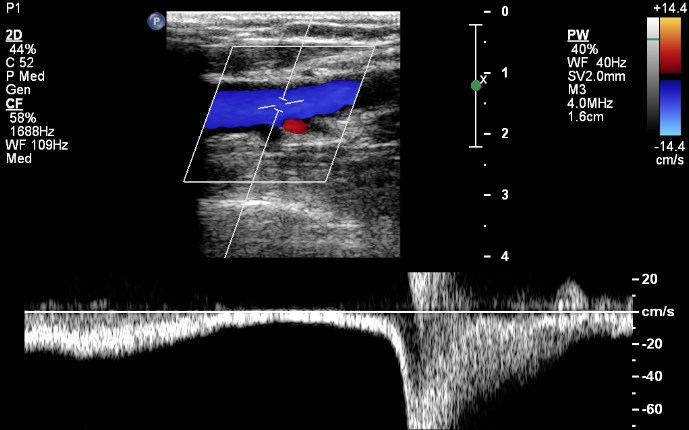

Pictures of Venous Reflux Ultrasound Images

Extremity - Lower Extremity Venous 2 If the examinations is performed to rule out venous reflux, obtain spectral Doppler tracings without/with Valsalva maneuvers or with proximal compression at the following locations: ... Retrieve Here

Venous Reflux Evaluation Patient Demographics limbs to obtain good quality images of —In order to standardize measurements of venous diameter and reflux, it is recommended that examination of the superficial veins is performed ... Return Doc